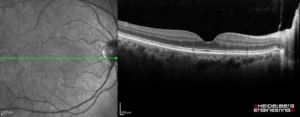

Η οπτική τομογραφία συνοχής (OCT) είναι μία από τις πλέον σύγχρονες και χρήσιμες απεικονιστικές μεθόδους στην οφθαλμολογία, η οποία μπορεί να απεικονίσει τόσο το οπίσθιο όσο και το μπροστινό τμήμα του ματιού. Η OCT προσφέρει τη δυνατότητα λεπτομερούς χαρτογράφησης των λεπτων στοιβάδων της ωχράς κηλίδας, του οπτικού νεύρου, του χοριοειδούς χιτώνα, αλλά και δομών του προσθίου ημιμορίου, όπως του κερατοειδούς, του προσθίου θαλάμου, του φακού και της ίριδας.

Η λειτουργία της οπτικής τομογραφίας συνοχής (OCT) συχνά παρομοιάζεται με αυτή των υπερήχων, δηλαδή χρησιμοποιεί την αρχή της αντανάκλασης πάνω σε ιστούς. Η διαφορά μεταξύ τους έγκειται στο ότι η OCT χρησιμοποιεί φως, ενώ οι υπέρηχοι τον ήχο ως μέσο. Το μηχάνημα OCT μετράει τον χρόνο καθυστέρησης από την αντανάκλαση του φωτός πάνω σε έναν ιστό, καθώς και την έντασή του, σχηματίζοντας τρισδιάστατη εικόνα σε όλη την έκταση και το βάθος του ιστού που είναι υπό μελέτη. Με άλλα λόγια, το OCT λειτουργεί ως μια μη επεμβατική ιστολογική εξέταση των οφθαλμών.